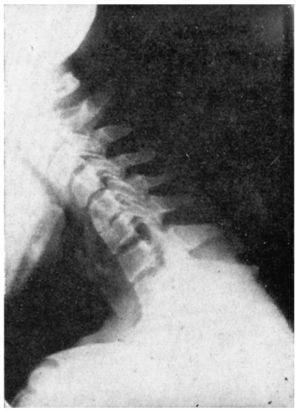

Hay que hacer radiografías de tipo funcional, es decir, de perfil en flexión y en extensión máximas, observando si además de una discosis hay hipermovilidad o inestabilidad en la columna cervical que se estudia.

La lesión es evidente en los discos con disminución evidente de su altura, con reacción ósea que ensancha las caras superior e inferior de las vértebras afectadas; los osteofitos se observan tanto en el borde anterior como en el posterior, algunas veces con evidente protusión hacia el conducto medular. Los discos más habitualmente afectados son el 5.o, 6.o, y el 7.o; también se afecta el 4.o, y 5.o, pero menos. Los discos afectados a veces son dos o tres, y a veces es sólo uno.

El síndrome clínico, lo mismo puede existir por irritación nerviosa o cálculo-nerviosa en el agujero de conjunción, por un osteofito pósterolateral o por una hernia discal media o lateral, así como por una inestabilidad vertebral cuyo exceso de movilidad provoca también un síndrome cervical. Por la tanto, en la observación radiológica tanto valor puede tener la discosis como la inestabilidad de alguna vértebra (fig. 2).

Figura 7 A.Caso núm. 6. M. Y. F. Inestabilidad de la quinta vértebra cervical.

Figura 7 B.Caso núm. 6. M. Y. F. Inestabilidad de la quinta vértebra cervical.

Figura 7 C.Caso núm. 6. M. Y. F. Comprobación a las cuatro semanas de la intervención. Bloque compacto de las 4, 5 y 6a C.